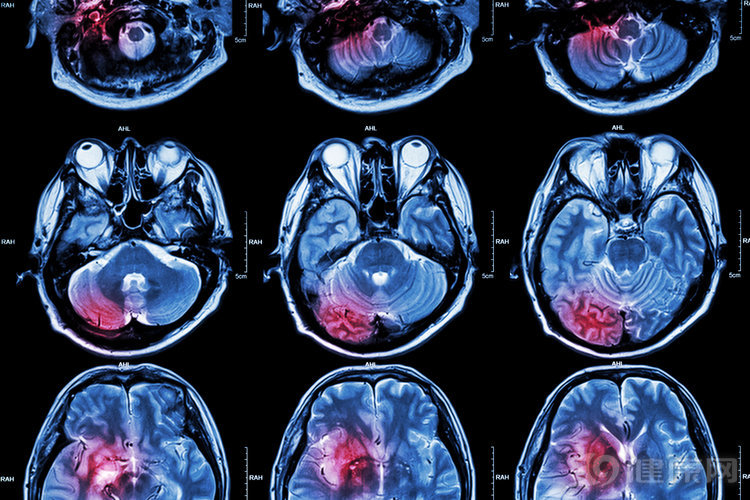

事实上,类似赵先生这样的情况在日常生活中并不少见,有时候突然出现的口眼歪斜,非常容易被人们所忽视。小中风,往往是由于颅内血管病变引起的短暂性、局灶性大脑或者视网膜的功能障碍。持续的时间最短几分钟,一般不会超过24小时,而且也不会留下后遗症。

从这些典籍记载中不难看出,小中风实乃中风的前兆。从小中风演变成中风,是一个由小到大、从轻到重的过程。而临床数据也证实,大约有30%的小中风患者最终会发展成中风,而有 4%~20% 的患者会在短暂性脑缺血发作(TIA)之后的三个月内出现中风。